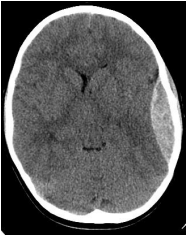

Um paciente de 23 anos chega ao pronto-socorro com perda de consciência após ser chutado na cabeça. Ele agora se encontra consciente e alerta e se queixa de cefaleia. A TC de crânio mostra a imagem ao lado. Logo após a TC, o paciente se torna não responsivo. Qual das seguintes é o próximo passo adequado na conduta?